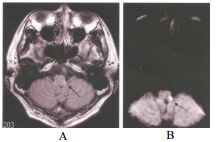

Wallenberg syndrome(也稱作 lateral medullary syndrome 或 posterior inferior cerebellar artery syndrome, PICA syndrome)是由延髓外側區域的梗塞所引起的腦幹症候群,常見原因為 椎動脈或後下小腦動脈(PICA)栓塞或血栓形成。

| 症狀類型 | 臨床表現 | 解釋 |

|---|---|---|

| ? 感覺異常 | - 同側臉部痛覺溫度覺喪失(CN V spinal tract) - 對側身體痛覺溫度覺喪失(spinothalamic tract) |

Crossing sensory loss |

| ? 動眼問題 | - 同側 Horner syndrome(ptosis, miosis, anhidrosis) | Sympathetic fiber involvement |

| ?⚕️ 小腦徵象 | - 同側共濟失調(cerebellar ataxia) | Inferior cerebellar peduncle |

| ? 吞嚥與聲音 | - 吞嚥困難(dysphagia) - 嗄聲(hoarseness) - 咳嗽困難 |

CN IX, X involvement (nucleus ambiguus) |

| ? 眼球與暈眩 | - 眩暈、嘔吐 - 眼震 |

Vestibular nuclei |